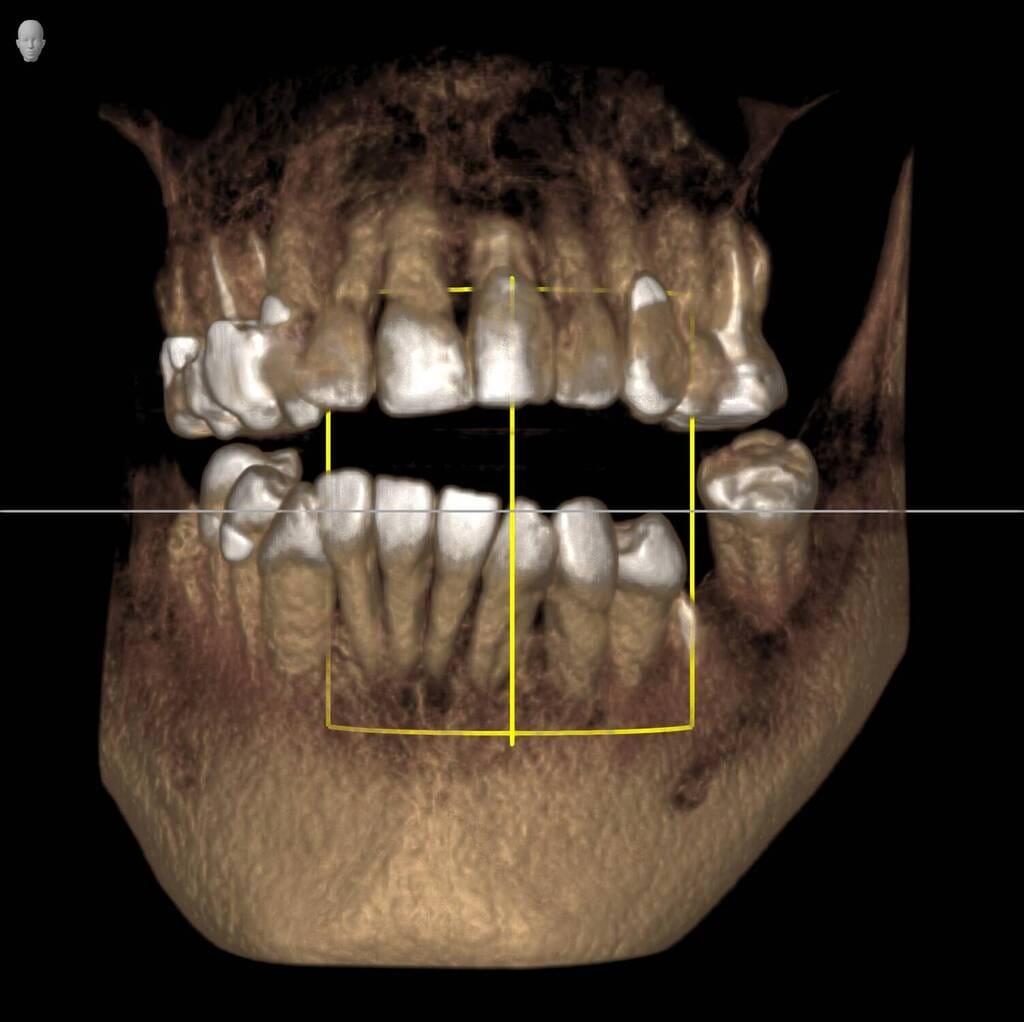

Natalie’s treatment began with a comprehensive clinical assessment, including a review of her medical and dental history, a full examination, and analysis of her functional difficulties such as her tongue habit and altered bite. A 3D cone-beam CT scan was then taken to assess bone quality and volume, identify areas of infection, and map important anatomical structures to ensure safe implant placement.

Alongside this, a digital intraoral scan and detailed photographic records were captured. These provided accurate models of her teeth and bite, as well as valuable information about facial proportions and smile aesthetics. Together, these records ensured that planning would address both the functional and cosmetic aspects of her rehabilitation.

All data were transferred into digital treatment planning software, allowing virtual placement of implants and collaboration with the dental laboratory before surgery. This enabled careful evaluation of long-term outcomes and ensured the design of provisional and final prosthetics could be completed with precision. Following these discussions, the decision was made to proceed with the Fixed-Teeth-in-a-Day approach using the All-on-4 technique.